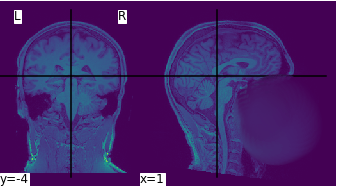

AI for neuroimaging

Study objective

Models

Modality

Epileptic focus localization

PET

Support Vector Machine

Functional connectivity mapping for schizophrenia

fMRI

Dynamic Causal Models

Unet

Brain tumor segmentation

MRI

Appukuttan, ..., Zaaraoui, Gilson 2025

multimodal fusion, interpretability